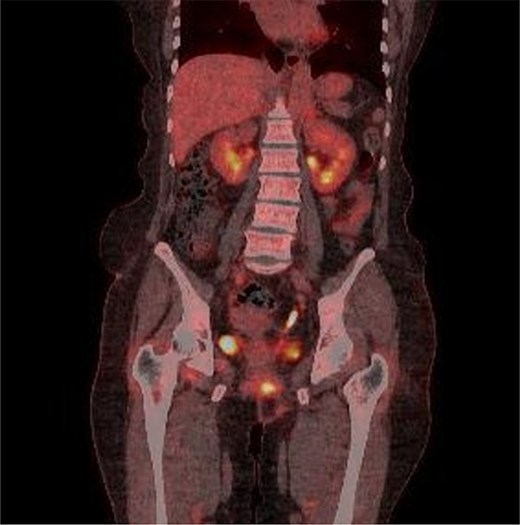

A 59-year-old female patient was referred to our hospital with severe left buttock pain lasting 5 days. Although she had no co-morbidities, she was previously diagnosed with hemorrhoids at the local clinic due to perianal pain persisting for 1 month. The patient had no medical or surgical history. Her initial body temperature was 38.4°C, blood pressure was 110/60 mmHg, heart rate was 98 beats/min, and her oxygen saturation was 98% on room air. On physical examination, erythema and hardness were noted in the left perineum and buttock areas. Additionally, dilated piles were observed on anus (Fig. 1). Given the clinical suspicion of FG, a computed tomography (CT) scan and blood tests were urgently performed. The CT scan demonstrated abscess formation along with severe emphysema in the left perineum and buttock (Fig. 2A). Blood tests showed leukocytosis of 41 840/μl with neutrophil left shift and an elevated C-reactive protein level of 33.4 ng/dl. The patient was finally diagnosed with FG, indicated by a severity index score of 6 points [6]. After initiating fluid resuscitation and broad-spectrum antibiotics, extensive debridement of the perineum was executed (Fig. 2B). However, due to clinical deterioration after general anesthesia, staged debridement was performed, and the patient was admitted to the intensive care unit for stabilization. Subsequent debridement and a diverting colostomy were performed 3 days after surgery. After 1 week in intensive care, the patient was transferred to the general ward where additional wound debridement and revisions were conducted. Two months after initial surgery, the surgical wound had completely healed, and wound closure was performed. Although inflammation had subsided, indurated tissue persisted around the anus, which had become so constricted that a digital rectal examination was impeded. Therefore, a biopsy of the perianal tissue was taken. Histopathological examination identified moderately differentiated squamous cell carcinoma, and HPV 16 was detected (Fig. 3). Pelvic magnetic resonance imaging (MRI) revealed anorectal cancer with invasion into both levator muscles and indeterminate lymph nodes in the bilateral external iliac, right obturator, and bilateral inguinal chains (Fig. 4). Positron emission tomography demonstrated an intensely hypermetabolic mass extending from the anus to the rectum, accompanied by multiple hypermetabolic lymph nodes in the left common iliac, left external iliac, right internal iliac, and bilateral inguinal regions (Fig. 5). Consequently, concurrent chemoradiotherapy (CCRT) employing mitomycin and 5-fluorouracil was initiated. The patient received a total radiation dose of 63 Gy in 35 fractions over 8 weeks. Elective nodal irradiation included the bilateral inguinal, internal iliac, and mesorectal nodal basins, in accordance with standard guidelines. Although follow-up MRI after CCRT showed a significant reduction in the size of the primary tumor and lymph nodes, we decided to perform a radical resection (Fig. 6). Robotic abdominoperineal resection was performed 3 months after CCRT, during which lateral pelvic lymph node dissection wasn’t conducted, as post CCRT imaging showed indeterminate lymph nodes suggestive of remission. Histopathological examination of the specimen revealed no residual tumor (ypT0N0). Although a minor surgical site infection occurred at the perineal wound, it was successfully treated with oral antibiotics and dressings at an outpatient setting. At 10 months post-surgery, the patient reported left pelvic pain, and follow-up imaging revealed suspected metastases in the left psoas, para-aortic area, supraclavicular node, right 10th rib, and lung. Consequently, the patient was scheduled for palliative chemotherapy.

Multiple intense hypermetabolic mass lesions identified from the anus to the rectum, accompanied by numerous hypermetabolic lymph nodes in the pelvis.